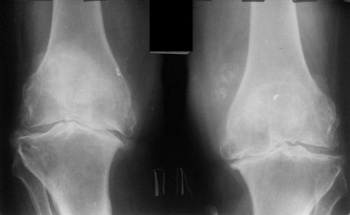

Prije dvije godine prvi put sam osjetila blage bolove u koljenima i kukovima. Bol nije bio jak, nisam posebno obraćala pažnju na to... Kako se pokazalo, bolesti zglobova su veoma ozbiljne i treba ih odmah liječiti, a ne odlagati kao ja! Jednog običnog dana osjetila sam ne baš jak, ali oštar bol u koljenima, a i kukovi su me ozbiljno počeli boljeti, mislila sam da je u redu, da će proći kao i uvijek. Kupila sam razne lijekove i masti i počela ih koristiti. Patila sam oko jednog tjedna , stanje mi se naglo pogoršavalo, bol je postao nepodnošljiv, počeo je akutni bol u kukovima, odlučila sam da se prvi put obratim ljekaru. Postavljena mi je ne jeftina dijagnoza, a moj ljekar je pogledao rezultate pregleda i rekao:

„Zašto ste ranije zanemarili simptome? Imate artrozu, artritis! Ako ne želiš da postaneš invalid, moraš hitno na operaciju kuka i koljena!"